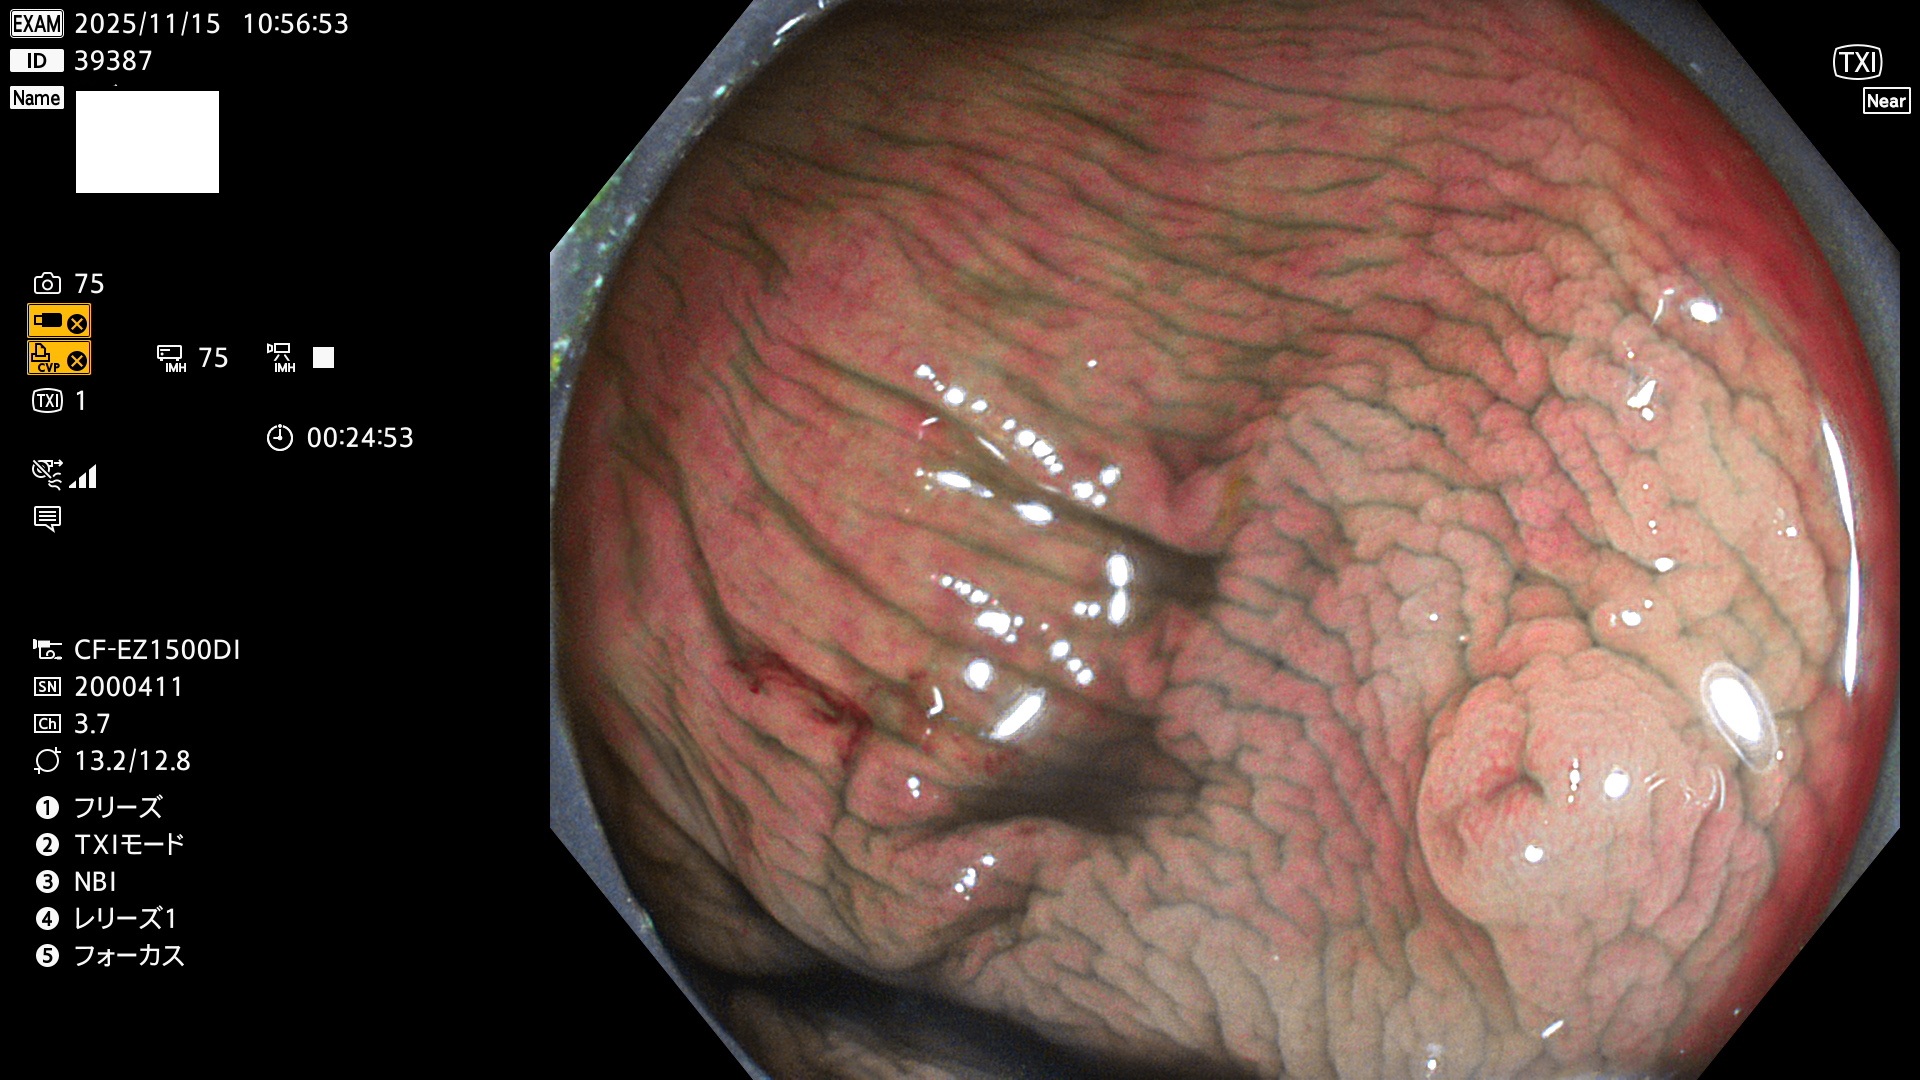

完全に平坦な物をUb、陥凹している物をUcと呼びます。Ubは認識が困難で、Ucはびらん(炎症)と紛らわしいために見落とされやすく、「内視鏡後・大腸癌」の原因になります。

毎週の検査(木・金・土・日)に発見されたUbとUc型・腺腫を、その週の日曜の夜にUPし1週間、提示します。

2025年11月13日〜11月16日の4日間(40件)4個 (Uc_ADR=4個/40人=10%)